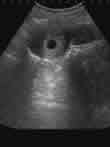

怀孕在5周-8周,胎儿和胎盘尚未形成,一般不需要扩张宫颈,是进行人流的最佳时机.

警惕:过早过晚都不适合做人流手术